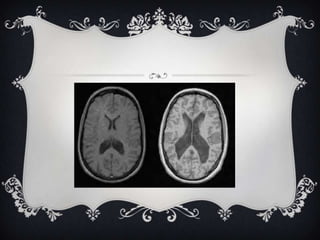

 Enlarged ventricles have been found in scans of the brains of

schizophrenic, leading scientists to draw correlations between the two

 Furthermore, activity in the frontal lobe appears to be slower than

that of a healthy human